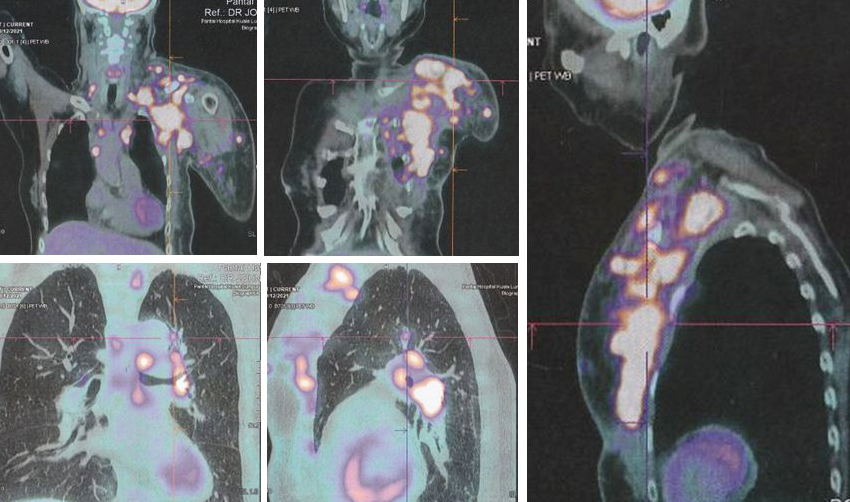

18. Hasil tes darah dan PET scan di rumah sakit swasta di Kuala Lumpur adalah:

• PET scan menunjukkan

• Kekambuhan lokal di dada kiri dengan baik,

• Metastasis ke kelenjar getah bening regional dan nodul subkutan, paru-paru, peritoneum dan tulang.

Seperti yang ditunjukkan oleh hasil kasus ini, Lucy telah mengambil jalan yang salah. Dua puluh bulan setelah melakukan apa yang menurutnya benar, kanker Lucy menyebar seperti api liar. Ada metastasis ke kelenjar getah bening regional, nodul subkutan, paru-paru, peritoneum dan tulang (lihat gambar di atas).

Saya mungkin mengatakan saya tidak percaya pada apa yang saya lihat di PET scan – itu benar-benar bencana yang mengerikan. Lucy telah melakukan kesalahan yang tragis.